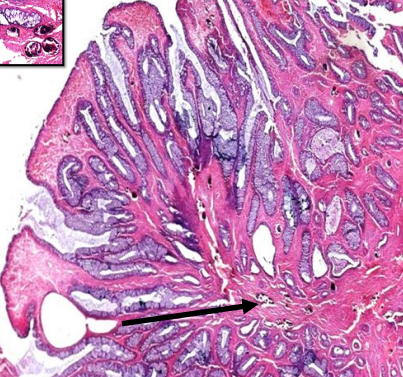

Section in? Describe Diagnosis?

Liver Liver is reduced in size. surface and cut section of liver are nodular. Has small regeneration nodule Regeneration nodule Liver cirrhosis